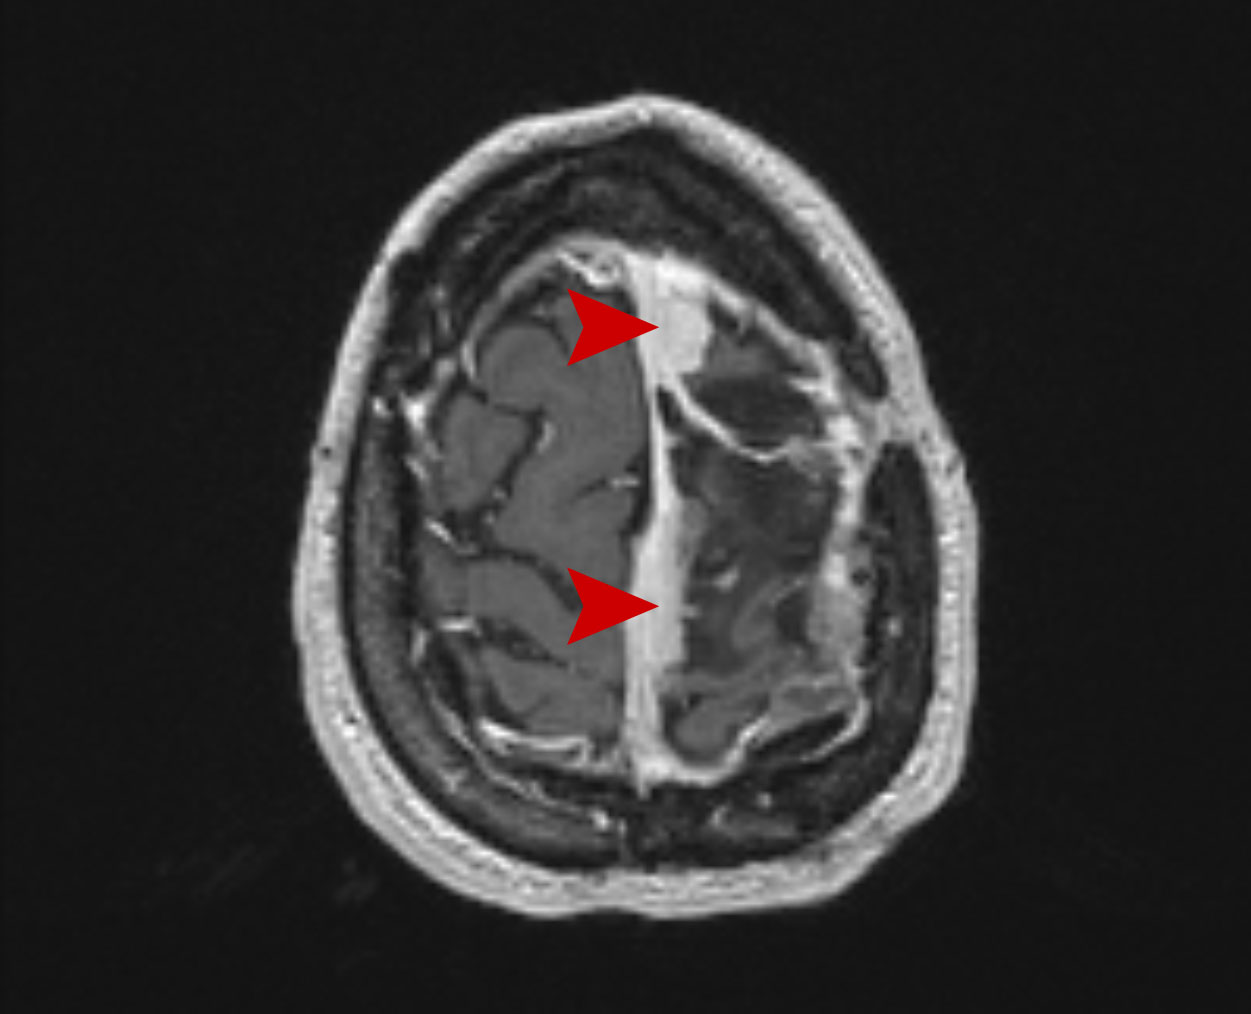

Μηνιγγίωμα Grade II Θεραπεία με CyberKnife #03

Θήλυ 40 ετών με υποτροπή χειρουργηθέντος Grade II μηνιγγιώματος σε πολλαπλές θέσεις των ορίων της…